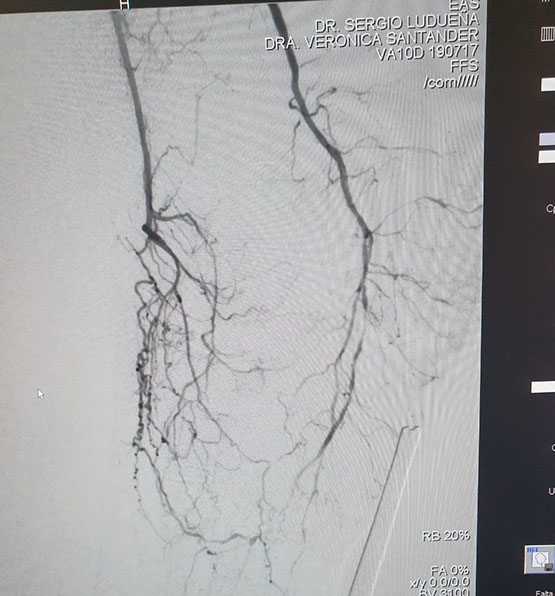

El Dr Sergio Raul Ludueña Jefe del Servicio de Hemodinamia de INCOR nos comentó sobre procedimiento realizado en el día de ayer en en el Servicio. "Queremos compartir con ustedes si bien no es un caso coronario , es un paciente obeso mórbido, diabético, con amputación supracondilea de miembro inferior izquierdo hace 3 años y actualmente con isquemia critica de miembro inferior derecho, con oclusión de ambas tíbiales y sin circulación en el pie".

Se realizó un abordaje híbrido con el Dr. Alejandro Flores, y se re canalizó ambas arterias tíbiales. Procedimiento inédito en nuestra provincia.

Las imágenes siguientes son previas al procedimiento y posterior se ve ambas arterias tíbiales permeables, y circulación en el pie

El procedimiento lo realizo el equipo de Hemodinamia de INCOR dirigido por el Dr. Ludueña junto con la intervención del Dr. Alejandro Flores (Flébologo y cirujano vascular)